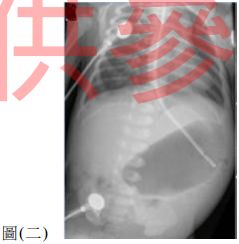

64. 6 週大嬰兒每次餵完奶不久就吐奶,已經兩星期了,身體檢查發現輕微脫水,上腹部可見 胃蠕動波 ( gastric peristaltic wave ) ,腹部超音波也證實正確的診斷。此嬰兒血液氣體分析 檢查 ( blood gas ) 下列何者最為可能? (A) pH 7.34, PaCO 2 60 mmHg ,

32 mmol / L (B) pH 7.48, PaCO 2 46 mmHg ,

34 mmol / L (C) pH 7.46, PaCO 2 25 mmHg ,

17 mmol / L (D) pH 7.32, PaCO 2 30 mmHg ,

14 mmol / L